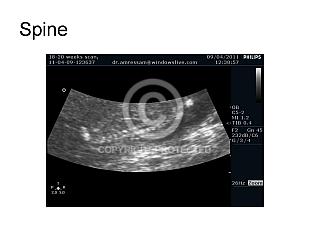

Fetal Spine and Limbs (16)

Standard views (7)

Spine and limb anomalies (9)